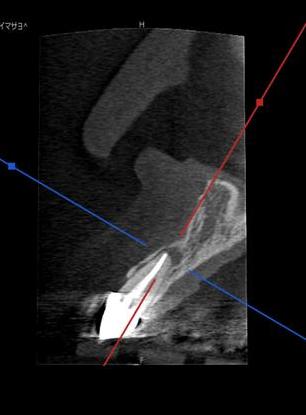

初診時のCTレントゲン写真です。

レントゲン写真を拝見すると根尖病変があり根の先に膿が溜まっているのが観察されます。

過去に行われた根管治療が失敗している状況で細菌が根管内にはびこっていることが原因です。